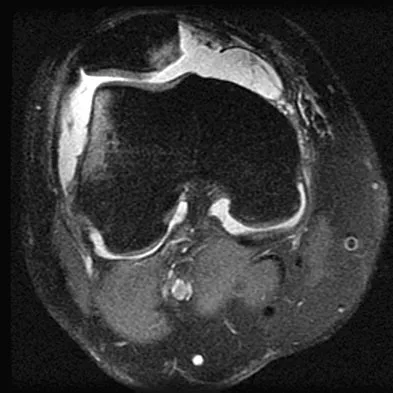

A 35-year-old woman who is a recreational runner reports posterior knee pain and tightness in the knee with flexion during running. She denies any history of trauma. Examination reveals normal patellar glide and tilt and no patellar apprehension. Range of motion is 5 degrees to 120 degrees, and quadriceps function and knee ligamentous examination are normal. Radiographs are normal. An MRI scan is shown in Figure 18. What is the most likely diagnosis?